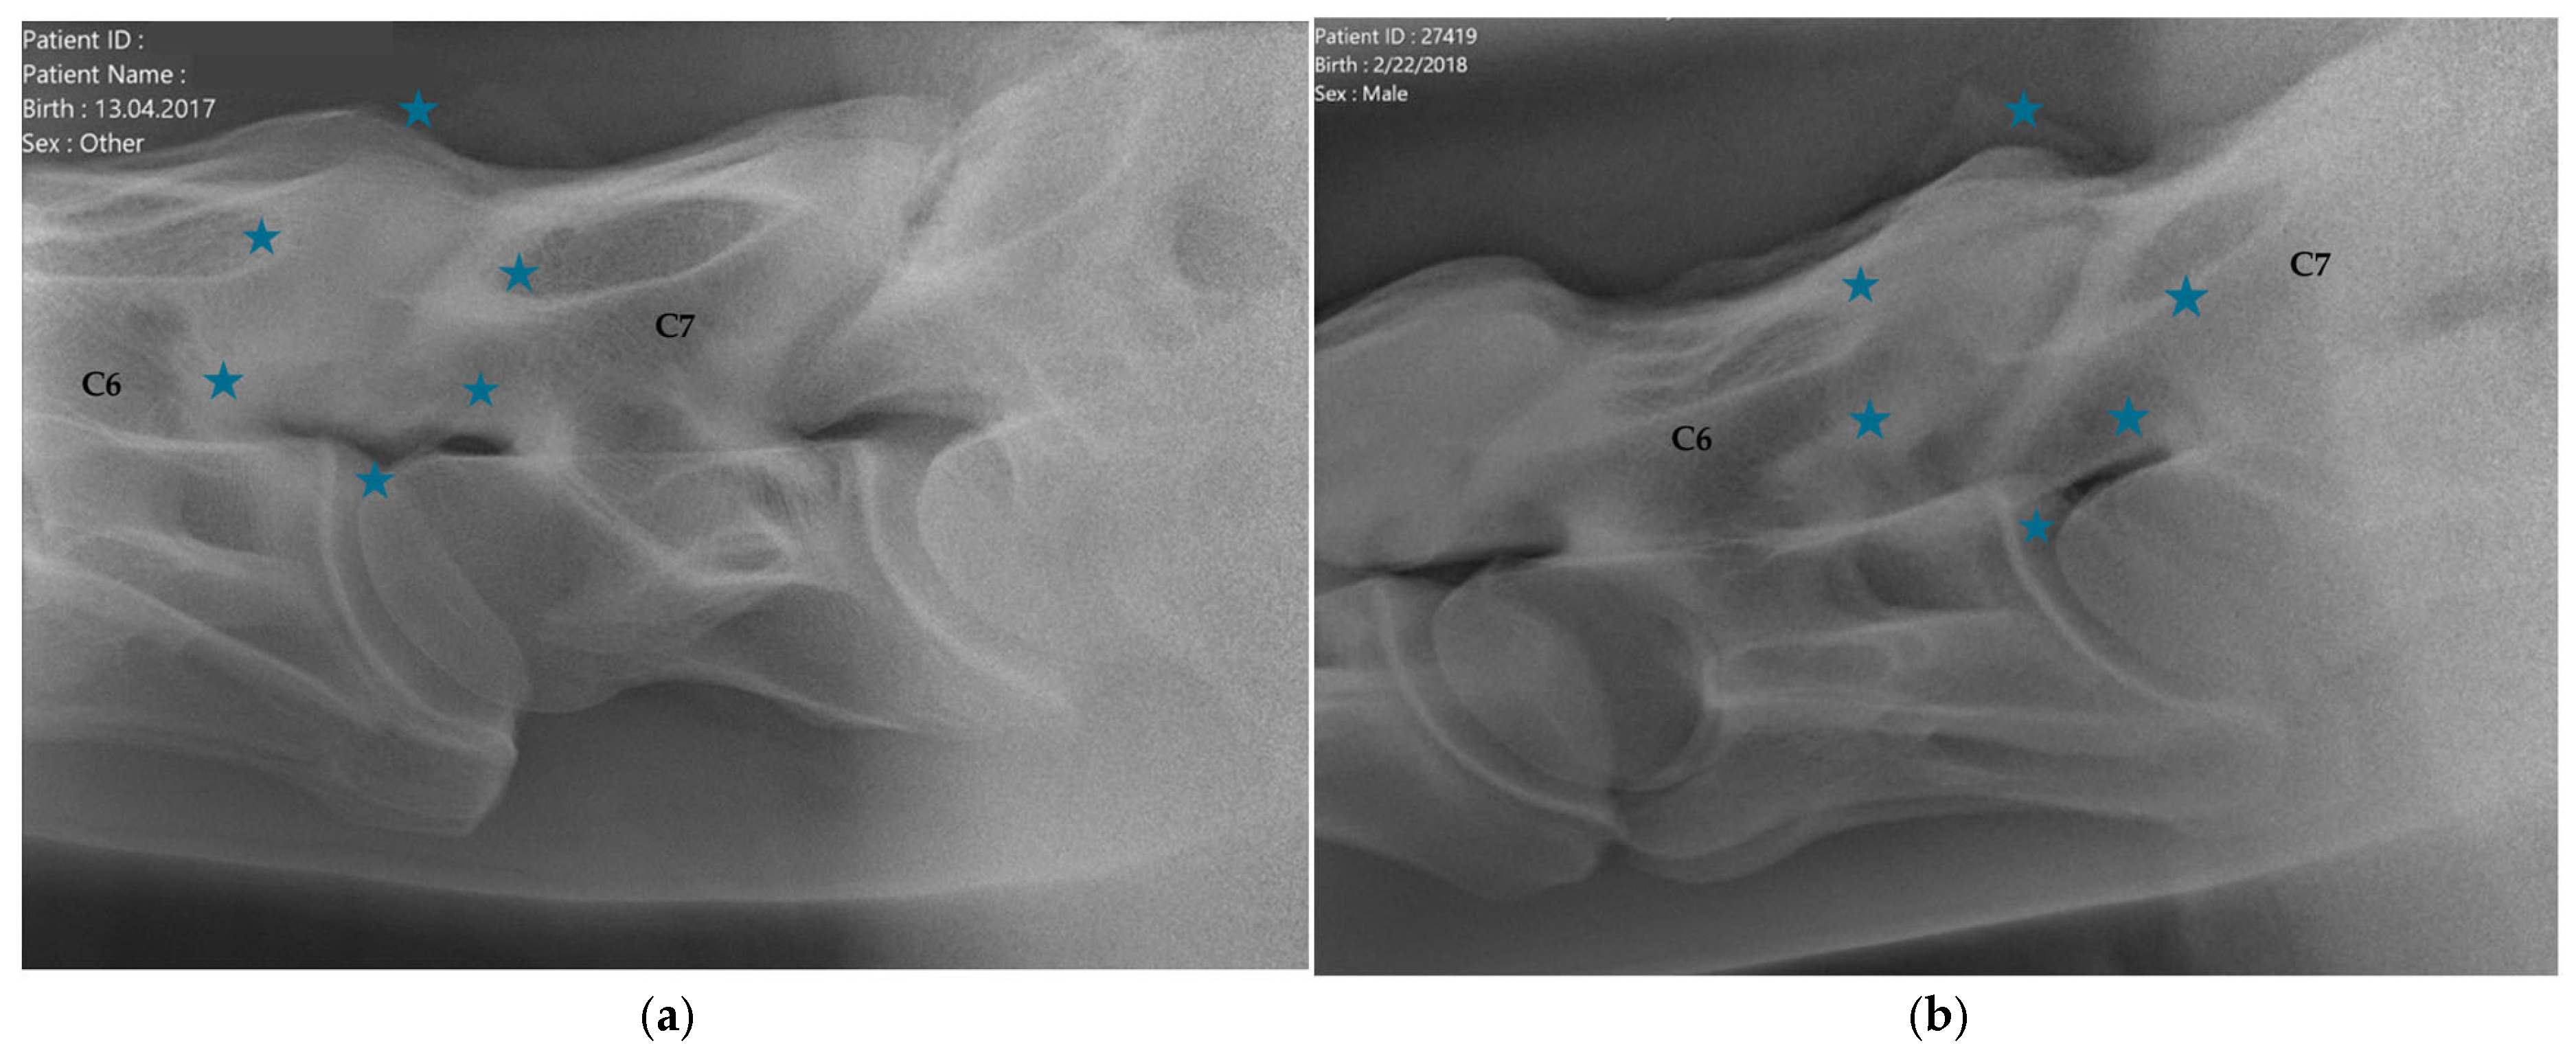

2.1.2. Radiographic Assessment

- Group 1 = normal: no periarticular new bone formation at ventral margins of APJ, intervertebral foramina clearly visible.

- Group 2 = mild APM: minimal/equivocal enlargement and sclerosis of APJ with mild osteophytosis ventrally, intervertebral foramina open/slightly obscured by new bone formation.

- Group 3 = moderate/severe APM: clear enlargement and sclerosis of APJ with moderate osteophytosis ventrally, significant reduction/loss of intervertebral foramina.